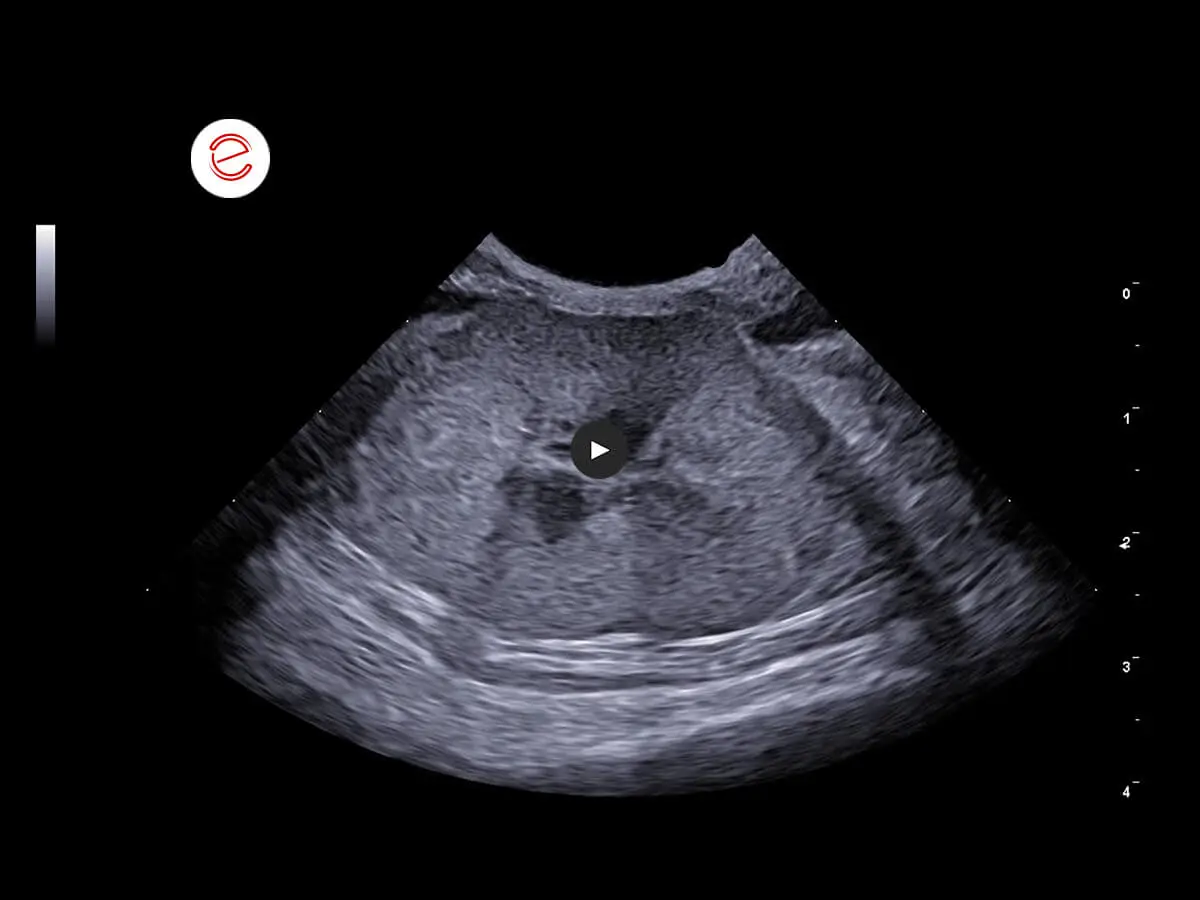

Right kidney: dimensions increased. Margins normal. No cortico-medullary distinction. Diffuse hypo-anechogenicity with findings of a hyperechoic band in which radially developing hyperechoic areas were reported.

Course of the right ureter in relation to the vessels. Ureteral ectasia observed throughout its course with diffuse wall thickening.

Diffuse omental hyperechogenicity associated with findings of layers of abdominal effusion with an anechoic appearance.